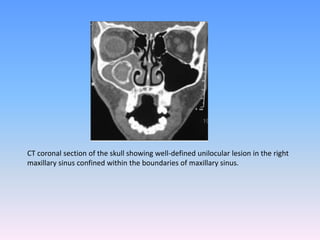

CT coronal section of the skull showing well-defined unilocular lesion in the right

maxillary sinus confined within the boundaries of maxillary sinus.